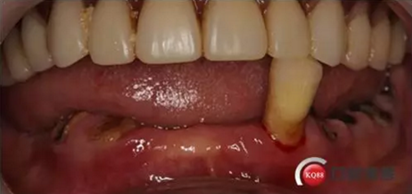

檢查:上頜無(wú)牙頜假牙穩(wěn)定性尚可,下頜3435364243殘根;33殘冠1-2度松動(dòng),其他牙齒缺失;CBCT檢查:下頜牙槽骨前牙區(qū)骨高度足,后牙區(qū)骨高度最低為8mm,骨寬度足。

1)術(shù)前檢查,拍攝臨床照片及CBCT檢查,制取活動(dòng)義齒參考模型,指導(dǎo)后期最終修復(fù)的牙齒排列

2)術(shù)前準(zhǔn)備及手術(shù)過(guò)程,測(cè)量血壓及血糖,簽種植知情同意書;嚴(yán)格遵循無(wú)菌操作,局麻下采用微創(chuàng)技術(shù)于323436分別植入osstem4.0X10,4.0X10,4.5X7; 434446分別植入osstem4.0X1O,4.0X10,4.5X7.初期穩(wěn)定性均達(dá)到了35N.CM以上;嚴(yán)密縫合,止血,種植體位點(diǎn)和方向與設(shè)計(jì)一致。